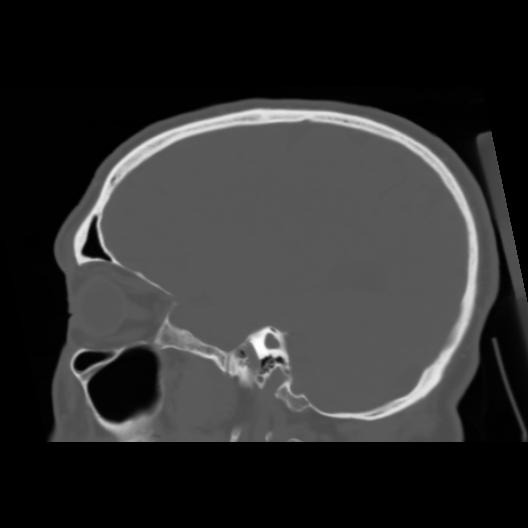

6 CEREBRO,,Sagittal,3.000,CEREBRO,Sagittal,